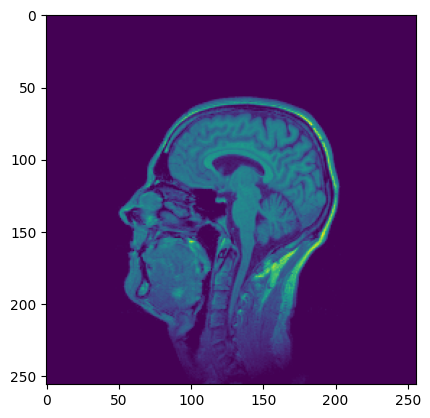

MRI画像(T1w)でテスト

t1 = download_and_extract_tiff_zip_to_ndarray("https://imagej.net/ij/images/t1-head.zip")

plt.imshow(t1[63, :,:])

K = 3 # 3クラス(白質、灰白質、脳脊髄液)

initial_labels = np.random.randint(0, K, size=(256,256)) # ランダムな初期ラベル

mu = [180, 340, 50] # 各クラスの平均輝度

sigma = [20, 7, 12] # 各クラスの標準偏差

estimated_labels = mrf_map_icm(t1[63, :,:], initial_labels, K, mu, sigma, get_neighbors_4, max_iterations=100)

今回は背景(空気や頭蓋骨など脳以外の領域)を含めているが、実際は頭蓋骨除去を行ってから処理するので、背景情報は無視できる。

平均値と標準偏差を適切に指定したり、処理前にデノイズしておいたりすることで、より精度を高めることができる。